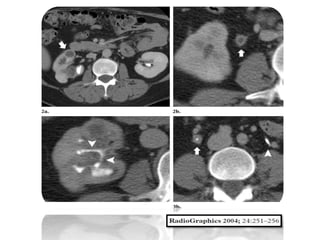

Riñones

La afectación bilateral se encuentra hasta en el 20- 30 % de los

casos.

En la radiografía simple, un tamaño renal variable puede

apreciarse.

Las Calcificaciones, que ocurren en más de 50% de los

pacientes, puede adoptar varias formas. Pueden ser

focales, que se producen en los restos de caseum, o como

cálculos en el sistema colector.

En los casos de tuberculosis en fase terminal, las

calcificaciones características que muestra una distribución

lobar son menudo encontradas.

En última instancia, un riñón totalmente calcificado y no util

puede verse, que representa etapa final de

enfermedad, denominada autonefrectomia.

Compromiso renal

Hallazgos coexistentes, tales como lesiones

destructivas de los cuerpos vertebrales y

calcificaciones de los tejidos y los músculos

paravertebrales (psoas) el contexto de un

absceso frío, se pueden encontrar.

Uréter

Un aspecto andrajoso adopta el ureter cuando se ve

afectado por la tuberculosis.

El uréter puede dilatarse, en respuesta a la obstrucción de

la unión ureterovesical, a reflujo vesicoureteral o

secundaria a la presencia de bacilos en su luz.

Múltiples sitios de estenosis se suelen

encontrar, generalmente afectando los sitio de

estrechamiento normal, comúnmente involucran al

tercio distal del uréter.

La calcificación extensa o engrosamiento del uréter

conocida como “ureter en tuvo de vastago”, cuando se

encuentra se suele relacionar con pionefrosis o

autonefrectomia.